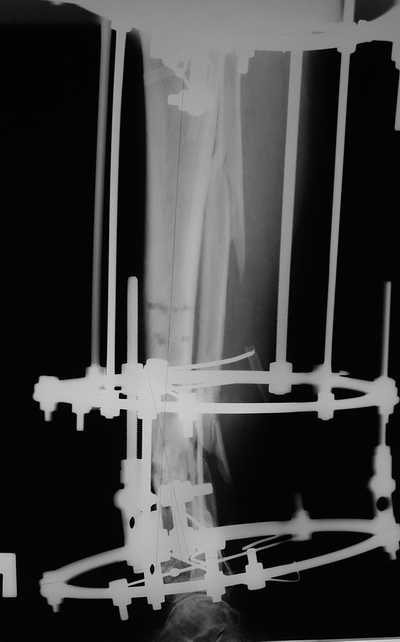

Male 54 years old, diabetic, blind in both eyes, with infected (MRSA) non union distal tibia after fracture 8 month ago. In acute phase treated by ORIF with LCP tibia and fibula. Treatment complicated by infection and after 6 month hardware was removed and treatment continued by cast fixation. You can see malposition of fragments In this stage beginning treated by Ilizarov fixation with use Hexapod system, allows anatomical position of fragments and you see signs of union.

Sorry, I wiil tray now pictures of my case.